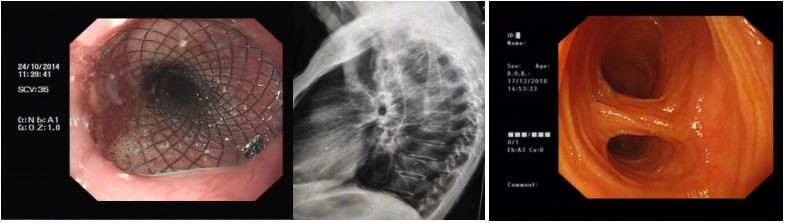

2.经内镜逆行胰胆管造影(ERCP)及治疗技术

我院采用治疗性ERCP,涵盖乳头括约肌切开网篮取石、球囊取石、器械碎石术、胆道支架置入术、鼻胆管引流术等多项微创技术,适用于胆总管结石、胆管癌或胰腺癌等多种疾病引起的梗阻性黄疸,取得较好临床治疗效果。具有安全、操作时间短、并发症少,术后恢复快等特点,为胆总管结石治疗的首选方案。

5.胃肠道狭窄扩张及支架置入术

消化道支架置入术适用于治疗由多种疾病引起的消化道良恶性狭窄的扩张及食道瘘的堵治疗。我科还开展了消化道碘125粒子支架植入术,除可以解除消化道梗阻外,对恶性肿瘤尚有放射治疗的作用,操作简单、安全、并发症少,是晚期消化道肿瘤患者不错的选择。

ERCP技术:鼻胆管引流术、胆道结石取术、胆道塑料及金属支架置入术

食管支架置入术                                                                             小肠镜图片